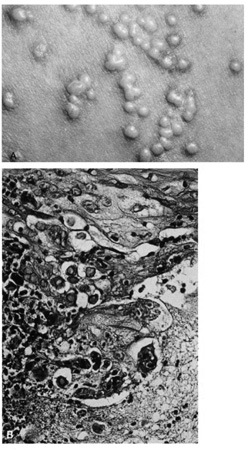

Umbilicated vesicles on an erythematous base progressing to pustules and crusted papules are characteristic of generalized vaccinia (small pox), with new cases recently reported secondary to the small pox vaccine. These vesicles are also characteristic of varicella (chickenpox), herpes zoster (shingles), and primary and recurrent herpes simplex infections (Fig. 6A). Herpesviruses are DNA-containing viruses that infect host cell nuclei resulting in similar, characteristic histologic changes. There is marked intraepidermal vesiculation and necrosis with massive ballooning and rupture of keratinocytes, spongiosis, acantholysis, and a dense superficial dermal perivascular lymphohistiocytic infiltrate with neutrophils, which also are seen commonly infiltrating the epidermis. Multinucleated epithelial giant cells with nuclei, which are steel gray and demonstrate peripheral margination of clumped chromatin material, are characteristic of early and well-developed vesicles (see Fig. 6B). Progression to near total epidermal necrosis makes these characteristic cells more difficult to identify. Occasionally, eosinophilic staining and small intranuclear inclusions may be visible. A Tzanck smear may be obtained by unroofing a vesicle, scraping the base, and staining the base with Giemsa stain. This rapid diagnostic method enables identification of multinucleated epithelial giant cells and single keratinocytes with characteristic nuclear changes. Lesions of molluscum contagiosum often affect the periorbital and lid skin as 1- to 3-mm domeshaped papules with a small central dell. This large pox virus multiplies in the cytoplasm, and, histologically, homogeneous purple intracytoplasmic inclusion bodies (molluscum bodies) are seen in an acanthotic epidermis (see Fig. 7). Verruca vulgaris (warts) are caused by a variety of papilloma viruses and may present as small papules with a digitated surface or elongated filiform warts around the eyes. Histologically, they demonstrate varying degrees of massive papillomatosis, hyperkeratosis, and acanthosis with parakeratosis and collections of serum in the stratum corneum at the tips of the digitations (Fig. 8). In early warts, the keratinocytes in the granular layer and just beneath the granular layer are vacuolated with condensation and clumping of dark-staining keratohyaline granules and occasional eosinophilic inclusion bodies in the nuclei. |